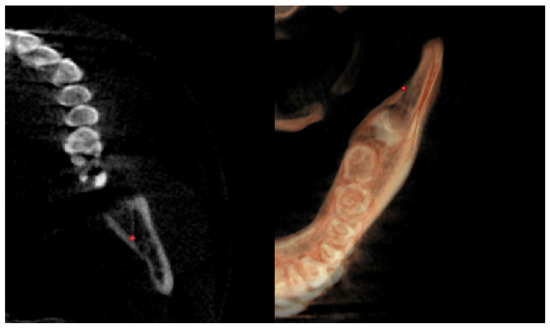

| Right lingual tuberosity (rLT) | / | The most posterior point (apex) of the retromandibular triangle, right side (Figure 5) | / |

| Left lingual tuberosity (lLT) | / | The most posterior point (apex) of the retromandibular triangle, left side (Figure 5) | / |